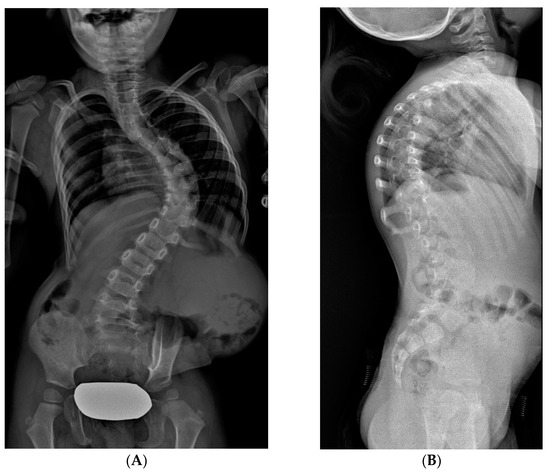

2.3.1. TGR: Traditional Growing Rods

2.3.2. MCGR: Magnetically Controlled Growing Rods

2.3.3. VEPTR: Vertical Expandable Prosthetic Titanium Rib